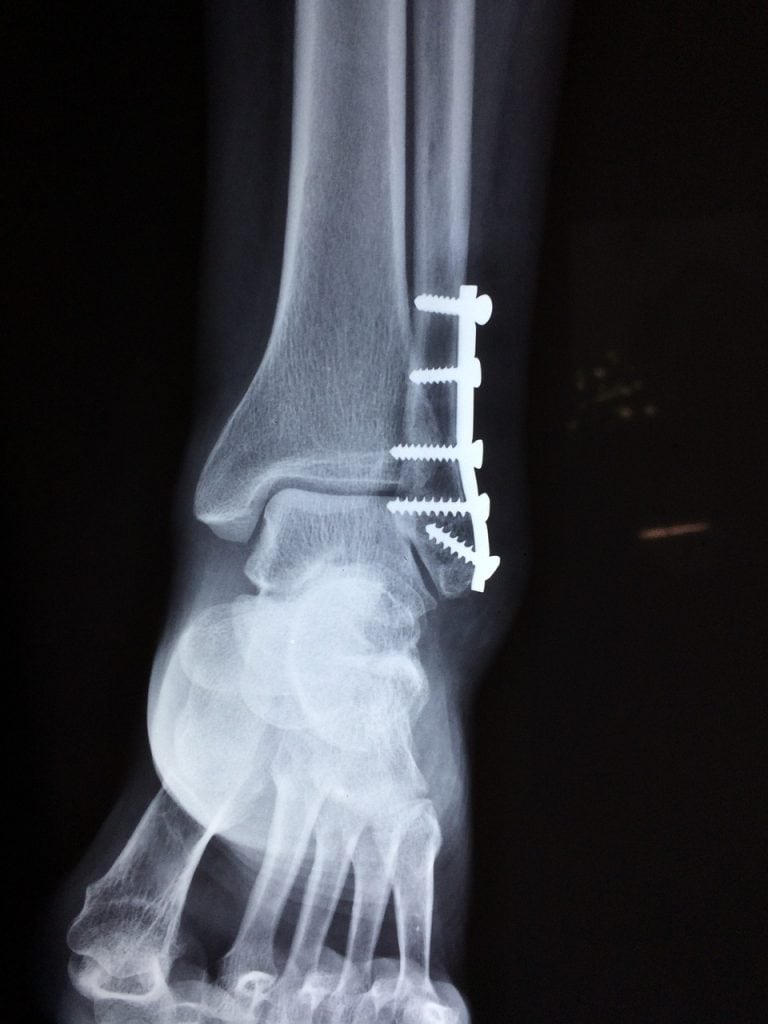

La oxigenoterapia hiperbárica (OHB) puede ser una herramienta valiosa en el manejo del síndrome compartimental, especialmente en casos agudos o crónicos donde la reducción del edema y la mejora en la oxigenación de los tejidos son críticas. El síndrome compartimental ocurre cuando la presión dentro de un compartimiento muscular aumenta, comprometiendo la circulación sanguínea y provocando daño a los nervios y tejidos. La OHB funciona al aumentar significativamente la cantidad de oxígeno disponible en el plasma sanguíneo, lo que ayuda a reducir la inflamación, mejorar la circulación y promover la recuperación de los tejidos comprometidos.

En el tratamiento del síndrome compartimental, la OHB suele administrarse a presiones de 2.0 a 2.5 ATA (atmósferas absolutas) durante 60 a 90 minutos por sesión. El número de sesiones puede variar dependiendo de la severidad del caso, pero típicamente se inician con 10 a 20 sesiones en un curso intensivo, seguido de evaluaciones para determinar la necesidad de sesiones adicionales. La OHB no solo ayuda a reducir la presión y el edema dentro del compartimiento afectado, sino que también acelera la curación y disminuye el riesgo de complicaciones como necrosis tisular o amputación. Este enfoque complementa los tratamientos convencionales y, en muchos casos, permite una recuperación más rápida y completa.